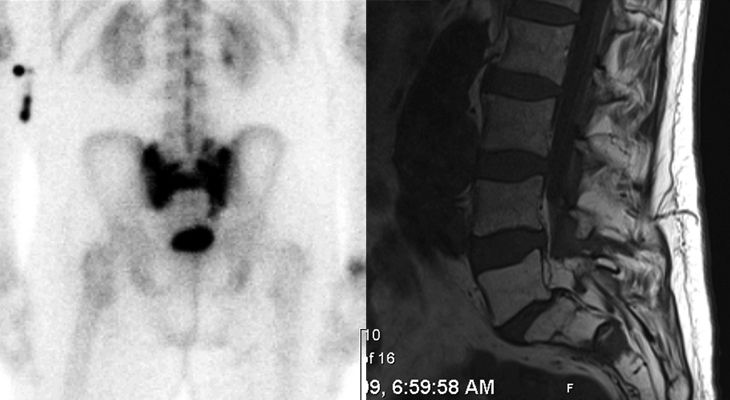

A 70-year-old man with a history of localized prostate cancer treated with whole-pelvis radiation therapy with a boost to the prostate, in conjunction with androgen deprivation therapy 7 years prior, presented with lower back pain. Evaluation by his primary care physician led to a bone scan, which revealed an area of activity in the sacrum. The patient’s prostate-specific antigen (PSA) level has been stable for the last 3 years. He has no other areas of pain and is otherwise healthy.

The nuclear medicine bone scan image is shown (left).